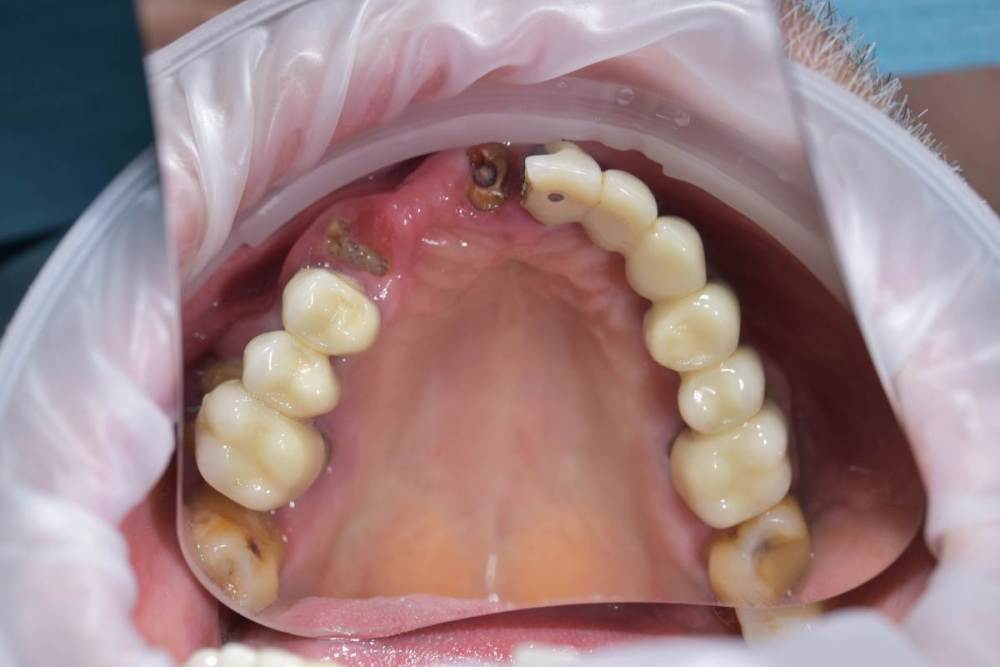

TIGER Опубликовано 13 июня, 2022 Поделиться Опубликовано 13 июня, 2022 (изменено) Всем привет!Довольно сложная исходная ситуация,пожелания пациента минимум вмешательств ,никаких костных пластик.В таких случаях я предпочитаю съёмные конструкции на балочной фиксации из-за возможности гигиены,ибо у так пациентов всё печально с этим.После обсуждения с пациентом он одобрил план действий и будущую конструкцию .Произведено изготовление шаблона,по навигации установлены импланты 4 верх и 4 низ,временные несъёмные конструкции на мультиюнитах,через полгода 2 протеза на балочной фиксации? Изменено 13 июня, 2022 пользователем TIGER 6 1 Ссылка на комментарий

TIGER Опубликовано 13 июня, 2022 Автор Поделиться Опубликовано 13 июня, 2022 Ситуация до Ссылка на комментарий